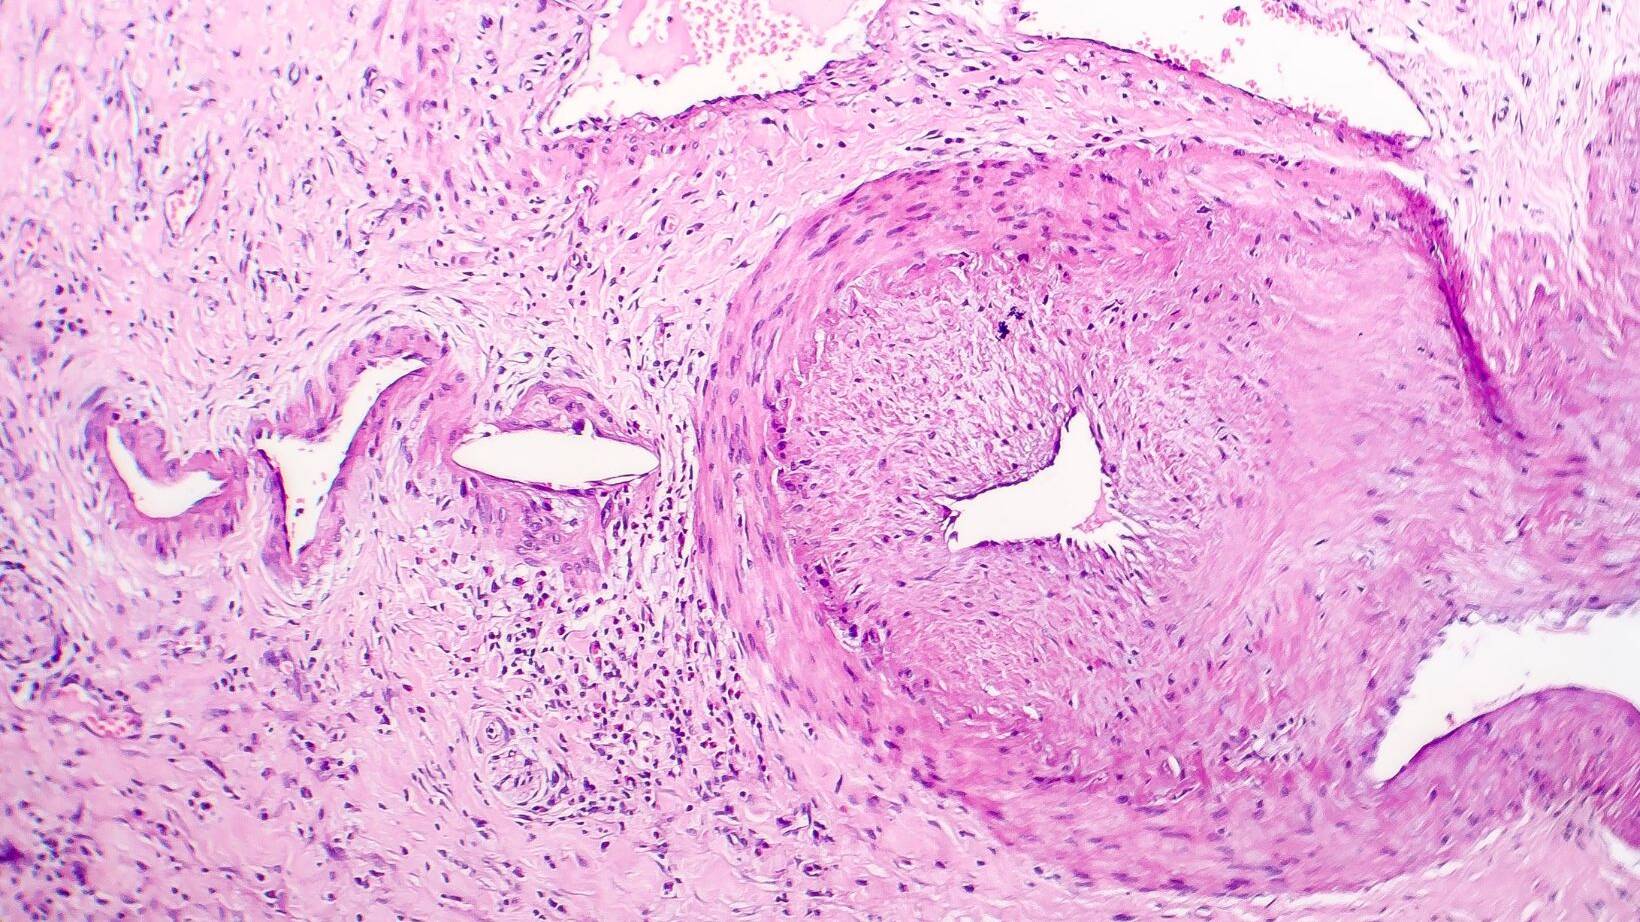

Understanding Colonic Polyps: Risks & Prevention

Welcome to our informative guide on colonic polyps. In this article, we will explore the risks…